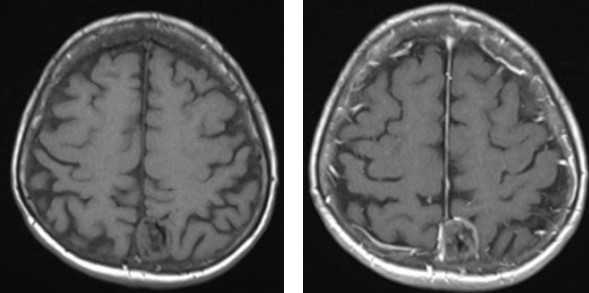

а — Т1-взвешенное изображение: ликвор гипоинтенсивный (темный)

б — Т2-взвешенное изображение: ликвор гиперинтенсивный (светлый)